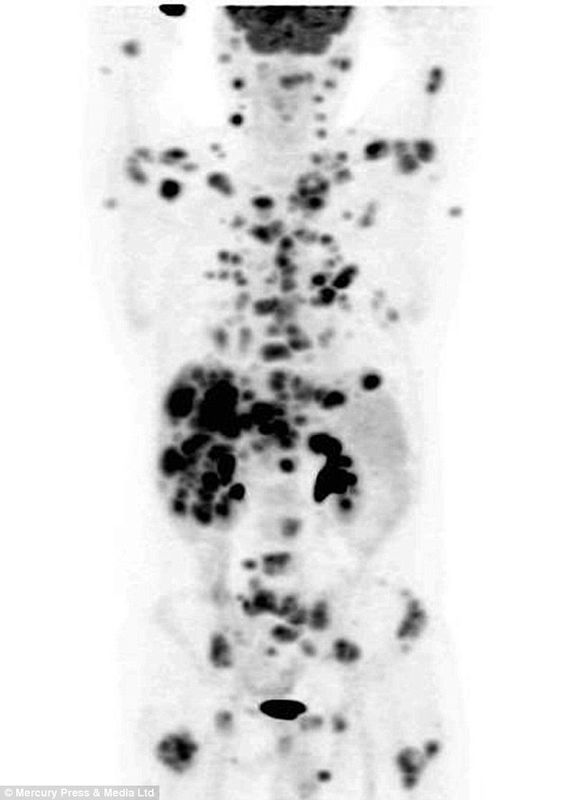

No, non è una bufala, o meglio questo comunicato che circola online è disinformazione che vorrebbe far credere si tratti dell’opera dei cattivoni della BigPharma! (GOMBLODDO!1UNO!!!SVEGLIA) Mercoledì 5 marzo a “Le Iene” su Italia1 è andato in onda un interessante servizio tutto documentato su come un signore malato di tumore sia riuscito a bloccare la […]